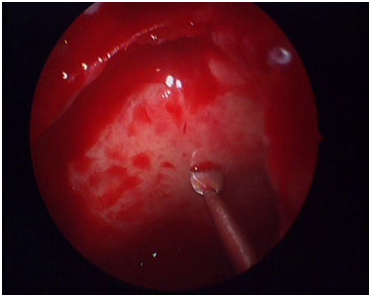

The rationale behind the preoperative treatment is the reduction of inflammation which will lead to less bleeding during the operation and therefore to more accurate dissection of the tissues.7 At the same time, the shrinkage of polyps and the reduction of mucosal edema will render the nasal cavities more accessible during endoscopic examination. It is now time for a second evaluation of the nose to decide in which nostril we will apply the dermoplasty technique. In the first three cases dermoplasty was applied in both nostrils. This resulted in a prolonged operation becoming cumbersome for the surgeon and dangerous for the patient. Then we decided to apply dermoplasty unilaterally planning to return to the contralateral nostril at a second stage. Our criterion as on which nostril to apply dermoplasty is the accessibility of the axilla of the middle concha which results in unobstructed insertion of the endoscope and the instruments in the middle meatus. Another effect of the preoperative treatment is the ability to study the anatomy of the ethmoidal labyrinth. At the end of the regimen the patient is submitted to a computed imaging (CT) of the nose and paranasal sinuses. The study of the CT will provide us with information about the anatomy of the ethmoidal complex and any areas of danger like the optical nerve, the internal carotid artery etc. The study of the CT will also permit us to estimate the surface and the contour of the skin graft needed. The radiologist will measure the distance between the posterior end of the frontal ostium and the sphenoid sinus (including its roof) in the sagittal plane (Figure 1) and then he/she will proceed to the coronal plane to measure the sum of the length of the lamina papyracea, the fovea ethmoidalis and the middle or upper concha at ten points moving from the posterior rim of the frontal ostium to the sphenoid sinus (Figure 2). The combination of these measurements will give the surface and the contour of the skin graft needed.

Figure 1 Working on the sagittal plane.